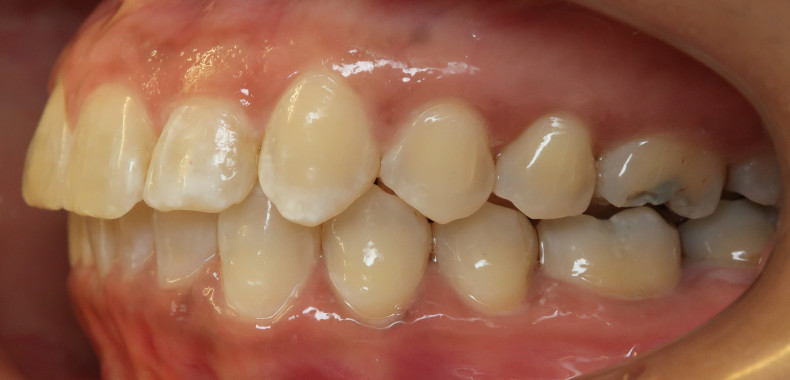

Der intraorale Befund (Abb. 2a–e) sowie die Modellanalyse (Abb. 3a–e) zeigten neben dem Diastema mediale im Oberkiefer vor allen Dingen eine Anteinklination und Supraokklusion beider Fronten. Besonders anterior wiesen beide Zahnbögen eine transversale Enge auf. Dies zeigte sich in einem deutlichen Unterkieferfrontengstand mit Labialkippung des Zahnes 41. Neben Abrasionen und Schlifffacetten, vor allem in der Front, waren auch vereinzelt Gingivarezessionen erkennbar. An Zahn 11 lag eine Schmelzfraktur der Inzisalkante vor. Durch die zwangsgeführte Laterognathie ergab sich eine Mittellinienverschiebung nach rechts von 3 mm. Eine beidseitige Distalokklusion bei vergrößerter sagittaler (6 mm) und vertikaler (5 mm) Stufe war erkennbar. Aufgrund der deutlichen transversalen Zahnbogenenge im Unterkiefer ergab sich links eine Tendenz zum Scherenbiss.